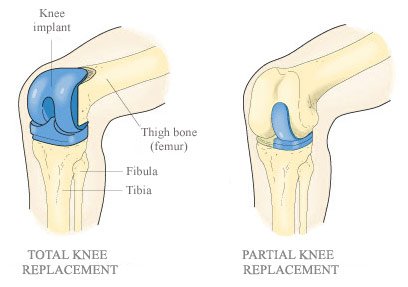

Het jy geweet daar is halwe én volle knievervangings? Met ‘n halwe knievervanging sny die chirurg nie deur spiere en sagte weefsel nie, en dus voel dit nog soos jou eie knie!

3. In sommige gevalle, waar net die binnekant of die buitekant van die kniegewrig verweer het, kan ‘n halwe knievervanging gedoen word. Met ‘n halwe knievervanging voel die knie ná die operasie steeds soos jou eie knie, omdat glad nie deur tendons, ligamente of spiere gesny word nie. Die knieligamente moet gesond wees om ‘n halwe knievervanging te kan doen.

4. Met ‘n volle knievervanging word wel deur die kruisligamente gesny.

7. Dis belangrik dat pasiënte ná ‘n knievervanging gereeld opgevolg word en as hulle pyn of iets vreemd ervaar, hulle na hulle dokter terugkeer, omdat die plastiekskyfie van die ‘bioniese’ knie in ‘n klein prosedure vervang kan word as dit afgeslyt word, en dan hoe die hele knievervanging nie oorgedoen word nie. Dit geld vir halwe en volle knievervangings.

8. Ná ‘n halwe knievervanging, kan ‘n volle knievervanging wel later gedoen word.